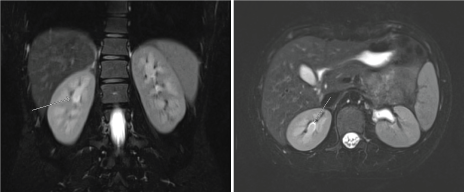

The patient underwent cystoscopy with bilateral retrograde pyelogram that revealed efflux of bloody urine from the left ureteral orifice, and filling defects in the left renal pelvic and lower pole calyx (Figure 1). The ureter was stented with a double J stent and subsequent ureteroscopy was performed. The patient was found to have renal papillae which were significantly hypertrophied and highly vascularized (Figure 2). The papilla of the lower pole calyx was hypertrophic to the point of protrusion into the renal pelvis. These hypertrophied lesions were biopsied and then ablated with a holmium laser. Pathology revealed benign fragments of renal medulla with tubular calcifications. MR angiogram performed one month later showed no vascular lesions or malformations. MR urogram showed prominent medullary pyramids in bilateral upper poles, consistent with renal papillary hypertrophy (Figure 3). The patient was followed without recurrence of hematuria for over 9 months.

Figure 3: MR Urogram showing prominent bilateral upper pole medullary pyramids consistent with papillary hypertrophy. Case 1-EC. View Figure 3

Patient underwent cystoscopy with retrograde pyelogram that revealed a filling defect in the upper pole calyx of the left kidney, but no lesion in the bladder or contralateral kidney (Figure 1b). A double J stent was placed with delayed ureteroscopy. On ureteroscopy, all the calyces of the left kidney were congested, enlarged, and demonstrated hypertrophic papilla (Figure 2b). Active oozing of blood was seen from the papillae in the upper pole calyx, which was ablated with a holmium laser. Patient was free of hematuria on follow-up for one month. She had recurrence of hematuria with MRI and MR urogram negative for pathology other than bilateral papillary hypertrophy. Patient's symptom of hematuria resolved and she is asymptomatic for 9 months.

Based on the previously reported case reports and our cases, it appears there is no one particular presenting feature of hypertrophied papillae. It is a rare variant that can sometimes cause essential hematuria. In our first case, the MR urogram revealed bilateral hypertrophied medullary pyramids; however, hematuria was unilateral. If the patient were to develop recurrence, a plausible explanation would be further growth and bleeding from the other papillae. Unfortunately, it is difficult to differentiate from upper tract tumors on radiographic studies, and thus requires an invasive and thorough work-up.